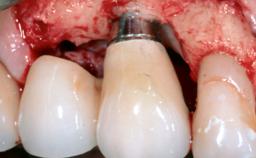

In this case, Mario Roccuzzo utilizes surgical bone regeneration treatment around implant 46 using a bone graft substitute and a connective tissue graft to resolve peri-implant inflammation, reduce the probing depths, and prevent further progression of disease.

A 58-year-old-male patient was referred in February 2007 for implant placement in the right mandibular molar area. Two tissue level implants were inserted at sites 44 and 46, respectively, to support a three-unit fixed dental prosthesis (FDP).